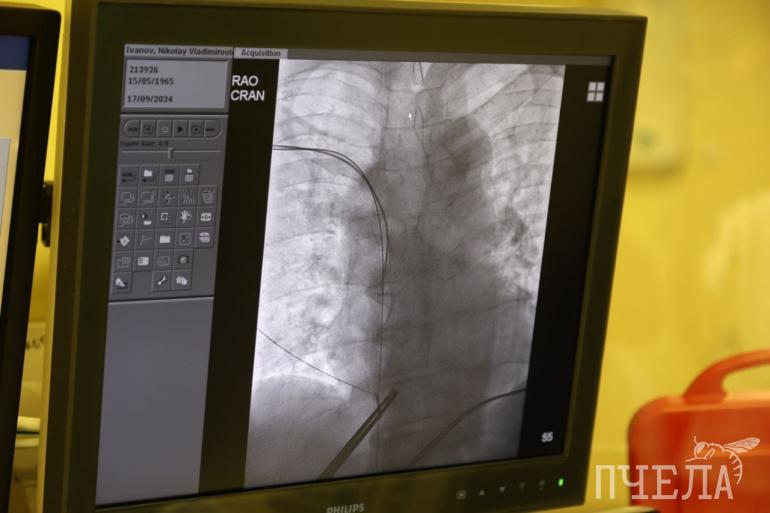

Установка оптимайзера — непростая задача для хирурга. Электроды должны попасть в нужный участок ткани и не задеть другие. Операцию проводят малоинвазивным способом под местной анестезией и с рентгенконтролем. Электроды вводятся в сердце через подключичную вену, а сам аппарат устанавливают в плече под кожей. Иногда позицию электрода приходится менять несколько раз, чтобы найти оптимальный участок.

— Целевая область установки электродов — межжелудочковая перегородка, но в процессе жизни структура перегородки меняется, нормальная живая ткань после перенесённых заболеваний превращается в фиброзную, или рубцовую, которая никак не реагирует на импульсы и не видит всю работу сердца. В процессе поиска два электрода ставятся в радиусе одного сантиметра, для этого находится оптимальное положение — наиболее живая и функциональная ткань. Электроды устанавливают обязательно в связке — сначала надо найти место для одного, а потом в допустимой области — для другого. Аппарат наносит высокую энергию в тот момент, когда сердце отдыхает и набирается сил — в рефрактерный период, когда происходит нормализация ионных каналов, таким образом он действует на клеточном и внутриклеточном уровне, — пояснил сердечно-сосудистый хирург КХО № 3 Челябинского кардиоцентра Василий Брюхов.